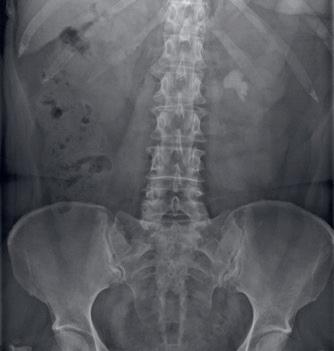

PROCES VAN MELDEN TOT FORMULEREN VERBETERMAATREGELEN

Het proces van melden van een calamiteit bij de inspectie tot aan het formuleren van verbetermaatregelen verloopt als volgt (figuur 2):

Meestal biedt het uitvoeren van een onderzoek uitkomst om duidelijkheid te scheppen. De zorgaanbieder heeft hiervoor maximaal zes weken de tijd. Indien na dit onderzoek nog steeds onduidelijk is of er sprake is van een calamiteit dan wordt geadviseerd om de gebeurtenis alsnog te melden bij de inspectie. Indien direct duidelijk is dat het gaat om een calamiteit, dan is de zorgaanbieder verplicht dit binnen drie werkdagen te melden bij de inspectie (artikel 11, 1e lid onder a).1 Door het melden geeft de zorgaanbieder openheid van zaken (figuur 2).

max 3 werkdagen melden bij inspectie

twijfel (advies is melden bij inspectie)

geen calamiteit

calamiteit gemeld

max 8 weken onderzoek

inspectie beoordeelt rapport en onderzoekt vervolg

geen calamiteit < 6 weken doorgeven aan inspectie

constateert geen calamiteit

calamiteit is voldoende onderzocht en verbetermaatregelen geformuleerd

nader onderzoek door inspectie

nader onderzoek door instelling

intrekken melding afsluiten melding

afsluiten melding en volgen eventuele verbetermaatregelen

inspectie doet zelf onderzoek

Figuur 2 Het melden van een calamiteit.2